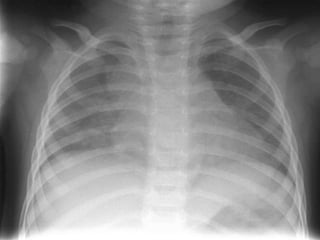

Rx tórax Niño: primoinfección. Patrón muy variable Adenopatías  hiliares ó mediastínicas: muy llamativas vs infiltrado Hiperinsuflación segmentaria y/o atelectasia (enfisema obstructivo <2 años)  Consolidación alveolar ó intersticial Derrame pleural  TBC miliar Adolescente: reactivación Cavitación Derrame pleural

Rx tórax Niño:primoinfección. Patrón muy variable Adenopatías hiliares ó mediastínicas: muy llamativas vs infiltrado Hiperinsuflación segmentaria y/o atelectasia (enfisema obstructivo <2 años) Consolidación alveolar ó intersticial Derrame pleural TBC miliar Adolescente: reactivación Cavitación Derrame pleural